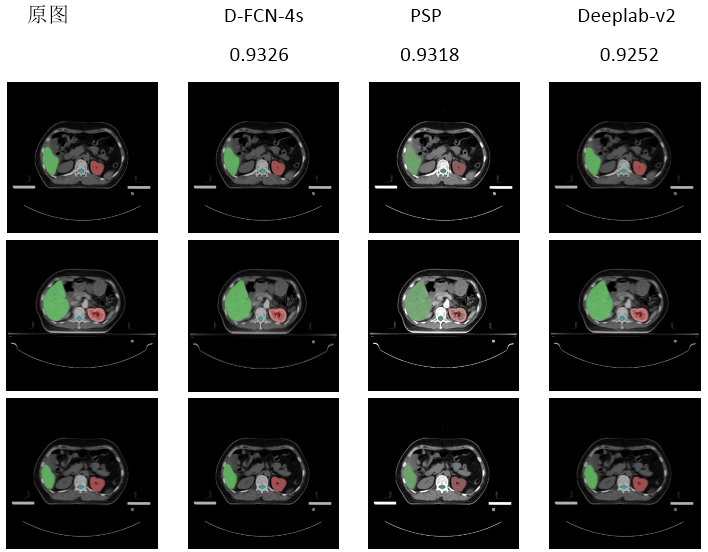

例如接纳FCN-深度学习模子�����,可对影像图像举行像素级的分类�����,提高了对正常组织器官和病灶的识别能力����。而基于深度学习手艺的自动勾画�����,相较于古板自动勾画手艺则具有重大的性能和准确性优势�����,大都人体结构的机械自动勾画平均准确率可抵达90%以上����。这不但使得医生的事情更为高效精准�����,越发推动放疗以致肿瘤医疗的智能化生长�����,增进肿瘤医学的前进����。

肿瘤靶区深度学习智能支解效果图